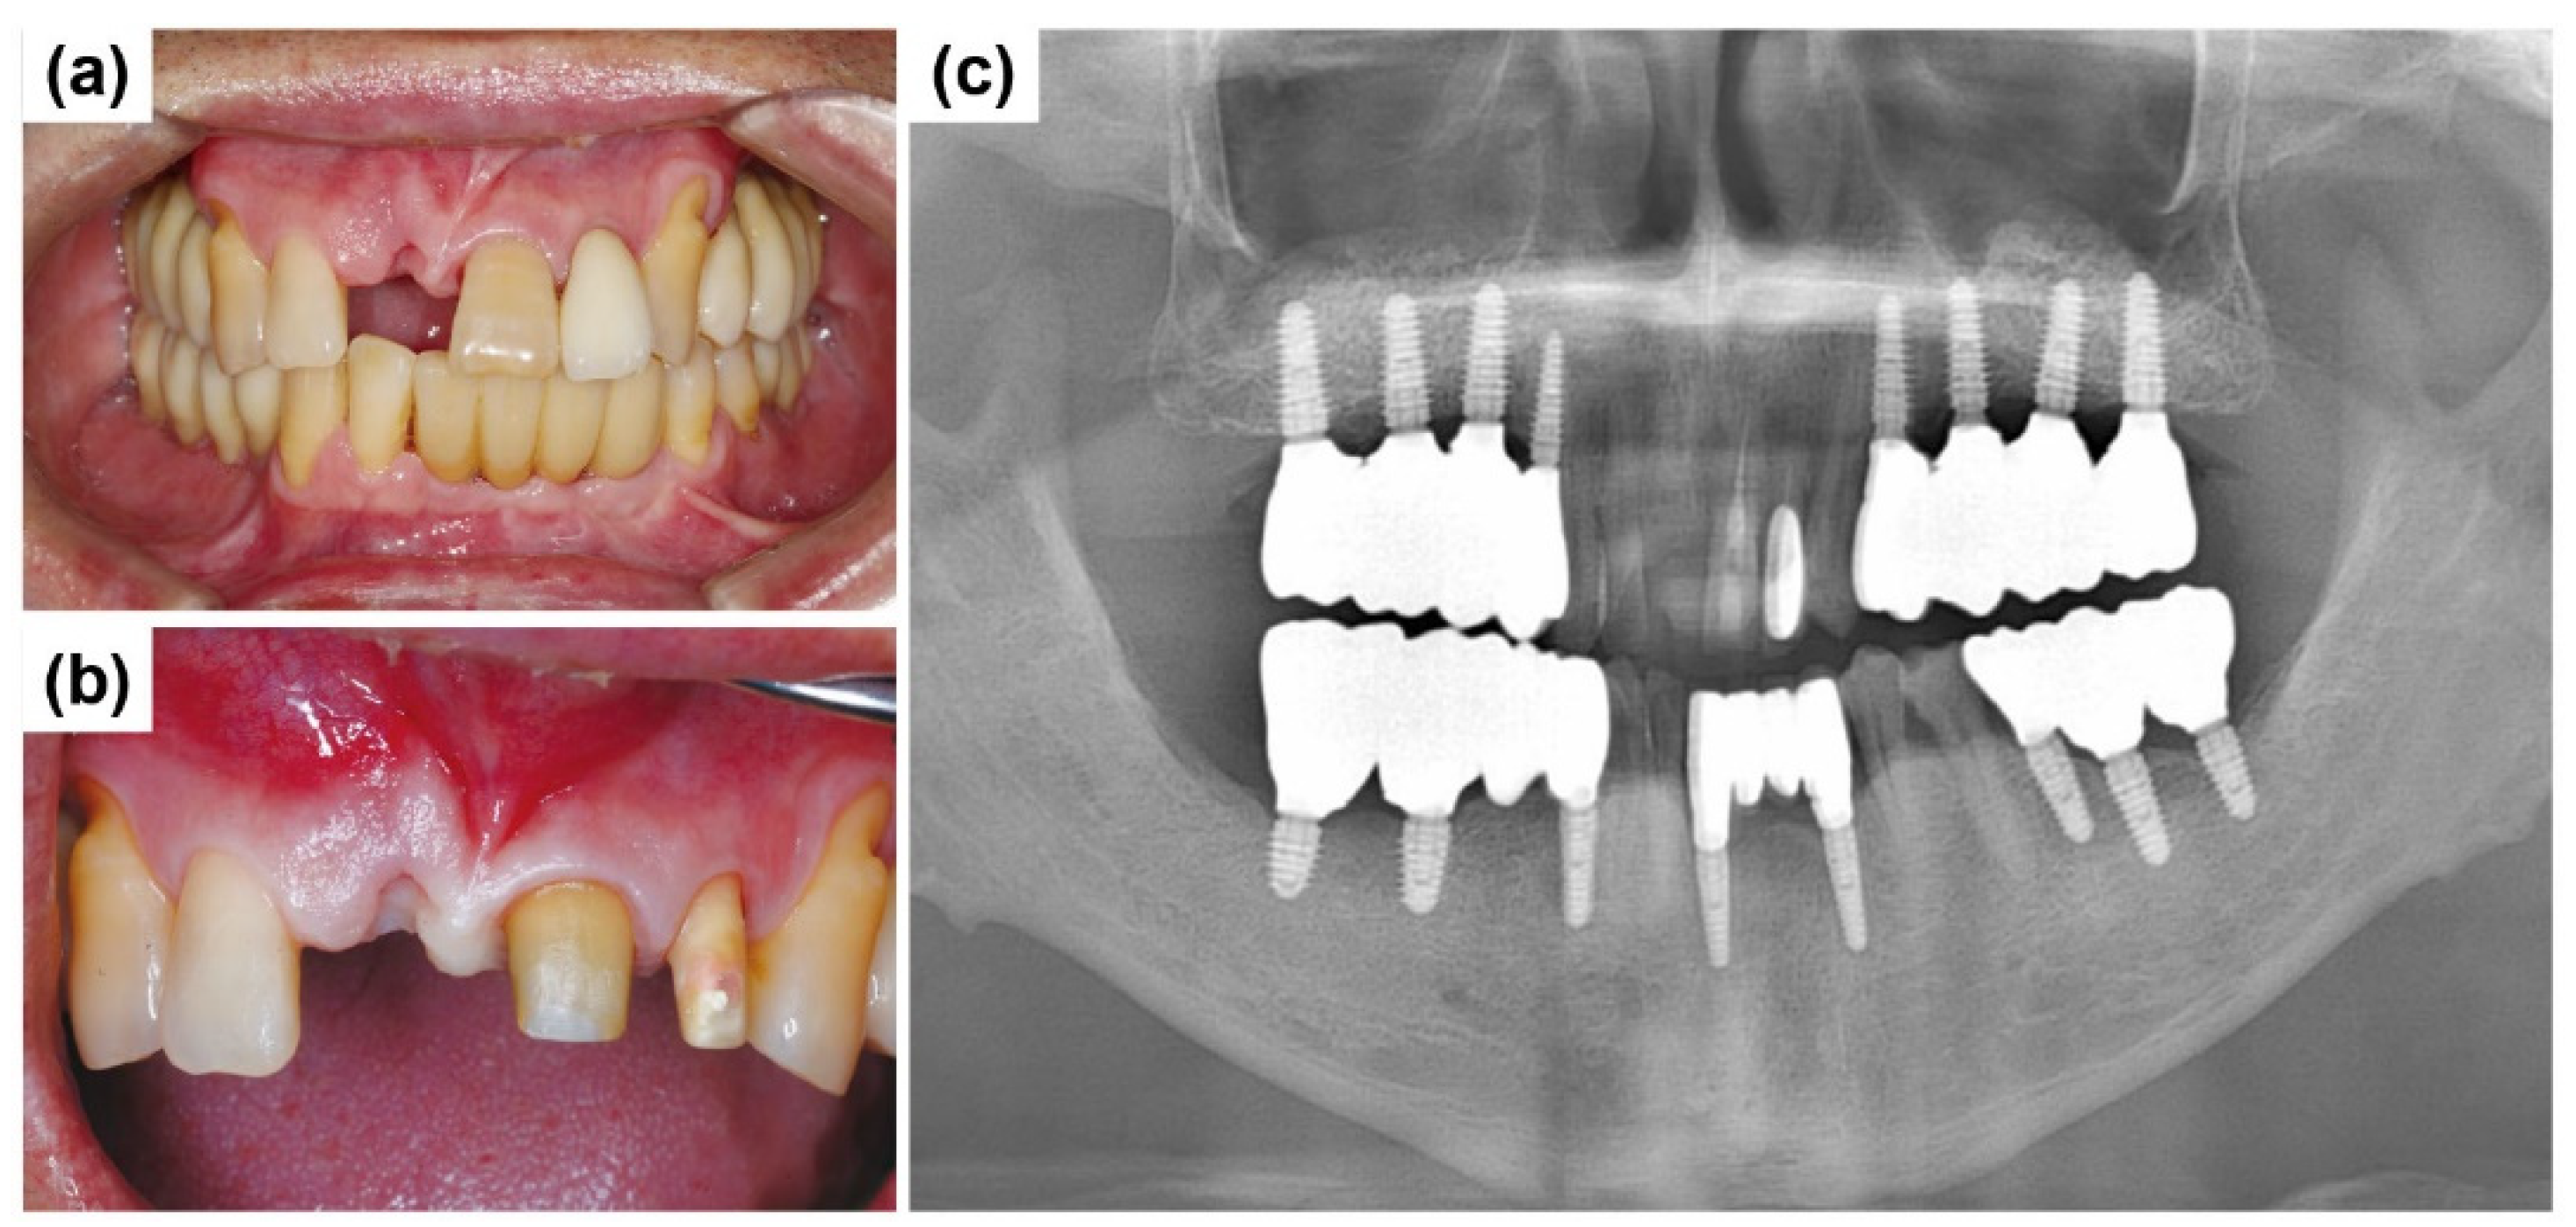

3. Results and Discussion